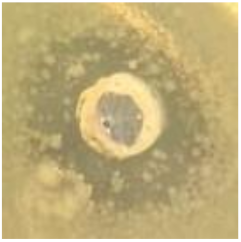

| AgNPs | 11.5 ± 1.7![]() | 10.6 ± 0.6![]() | 8.8 ± 0.5![]() | 8.8 ± 3.0![]() |

| Vancomycin | 22.5 ± 0.5![]() | 22.5 ± 0.5![]() | 8.0 ± 0.1![]() | 8.0 ± 0.2![]() |

| LL37 | 6.5 ± 0.1![]() | 6.5 ± 0.5![]() | 6.3 ± 0.1![]() | 6.2 ± 0.1![]() |

| Pexiganan | 9.0 ± 0.5![]() | 12.2 ± 0.6![]() | 8.0 ± 1.5![]() | 12.0 ± 0.1![]() |

| TTO | 20.2 ± 0.1![]() | 15.0 ± 0.5![]() | 15.5 ± 0.5![]() | 13.3 ± 0.3![]() |

| CLO | 21.5 ± 0.5![]() | 15.0 ± 1.0![]() | 15.0 ± 1.9![]() | 15.0 ± 0.6![]() |

| NO | 14.7 ± 0.4![]() | 10.0 ± 0.5![]() | 11.5 ± 0.5![]() | 6.8 ± 0.5![]() |